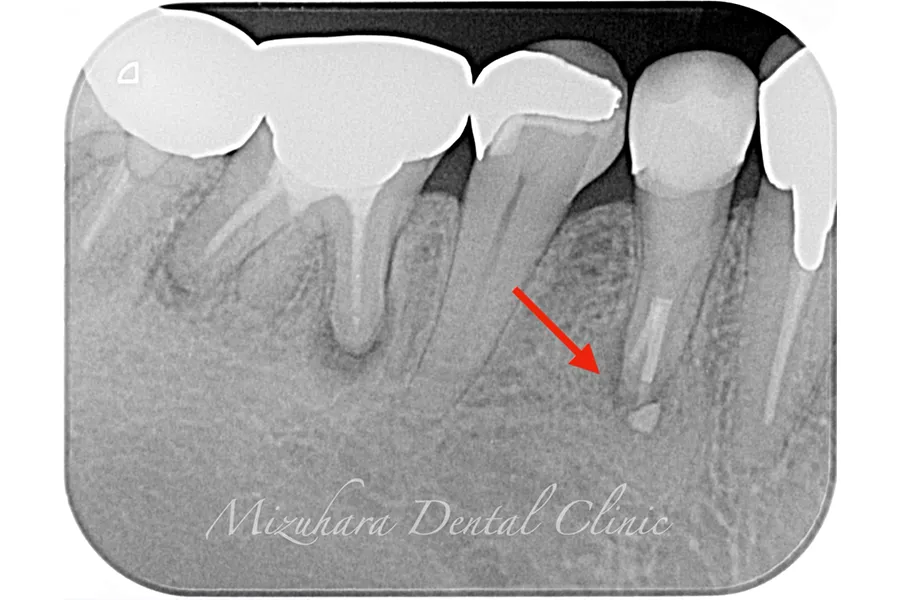

世界基準の成功率を目指した精密根管治療

根管治療

当院では豊マイクロスコープ、ラバーダムを使用し、世界基準の成功率を目指した精密根管治療による「歯を残す」ための治療をご提供します。